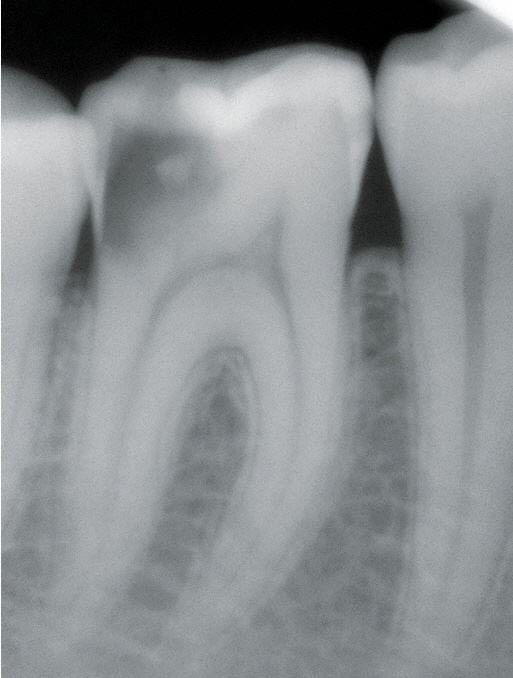

Die Anfertigung von Röntgenbildern ist in der Zahnheilkunde die wichtigste Voraussetzung für die Erstellung von Diagnosen und Behandlungsplanungen.

In unserer Praxis werden seit dem Jahr 1996 ausschließlich digitale Röntgenbilder hergestellt. Digitales Röntgen verzichtet auf Filme und Fotochemikalien. Stattdessen werden mittels eines Sensors, der den Röntgenfilm ersetzt, die Bilder in einen Computer geleitet. Dieser Vorgang benötigt nur Bruchteile von Sekunden.

Der Betrachter der Bilder kann diese vergrößern, Ausschnitte wählen, Kontrast und Helligkeit verändern sowie auf viele verschiedene Weisen das Bild verändern. Dadurch lässt sich eine absolut präzise Diagnose erzielen.